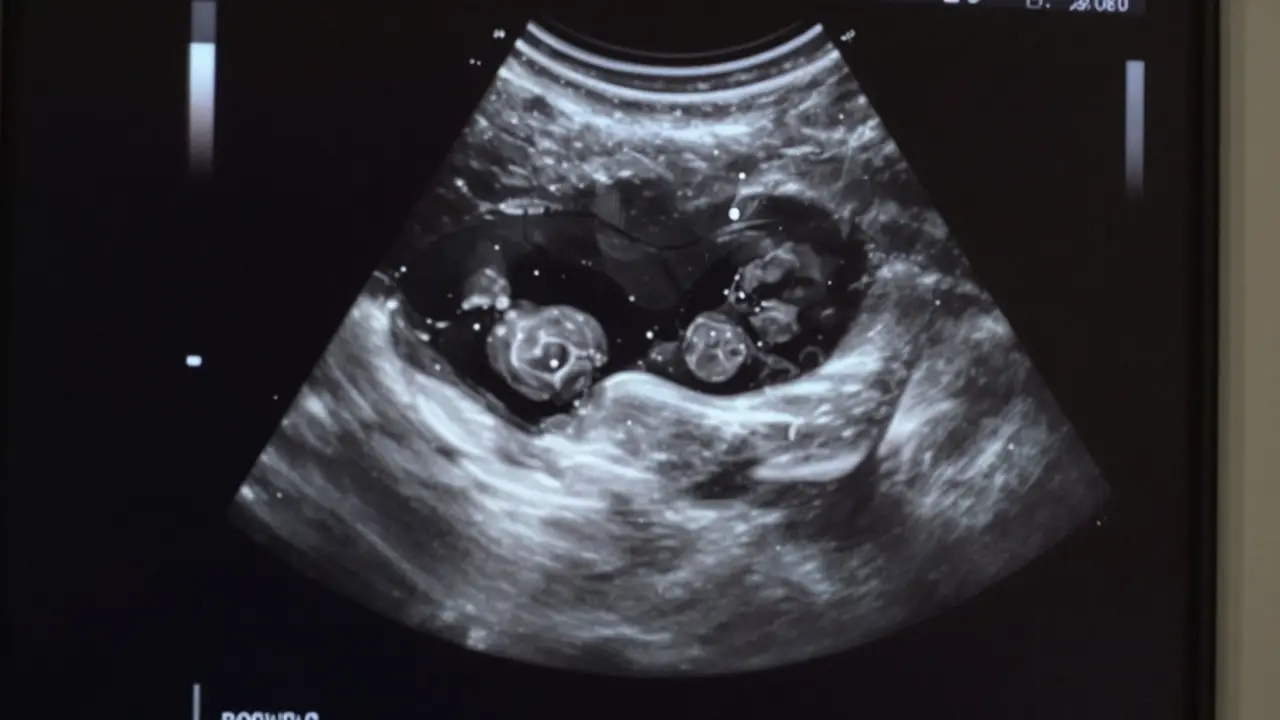

Co lze vidět na ultrazvuku v 5 týdnech?

Na transvaginálním ultrazvuku, který je v této fázi nejpřesnější, lze často vidět několik klíčových prvků:

• Plodový sac - to je první struktura, která se objeví. Je to malý, tmavý kruh v děloze, který označuje místo, kde se embryon bude vyvíjet.

• Žloutkový váček - malý, kulatý útvar vedle plodového sacu. Slouží jako zdroj výživy pro embryon před tím, než se vytvoří placentu. Jeho přítomnost je dobrým znamením, že vývoj probíhá normálně.

• Embryo - v některých případech, pokud je těhotenství přesně v 5 týdnech, lze vidět i malý, bílý tvar, který je embryem. Nejde o žádný „malý človíček“, ale o hustý kousek tkáně, který se postupně vyvíjí.

• Srdeční tep - to je to, co většina lidí čeká. Ve 5 týdnech je srdeční tep ještě velmi častý, ale ne vždy viditelný. Většina lékařů ho vidí až mezi 5. a 6. týdnem. Pokud ho ještě nevidíte, neznamená to selhání - jen to znamená, že embryon je ještě o něco mladší, než se předpokládalo.